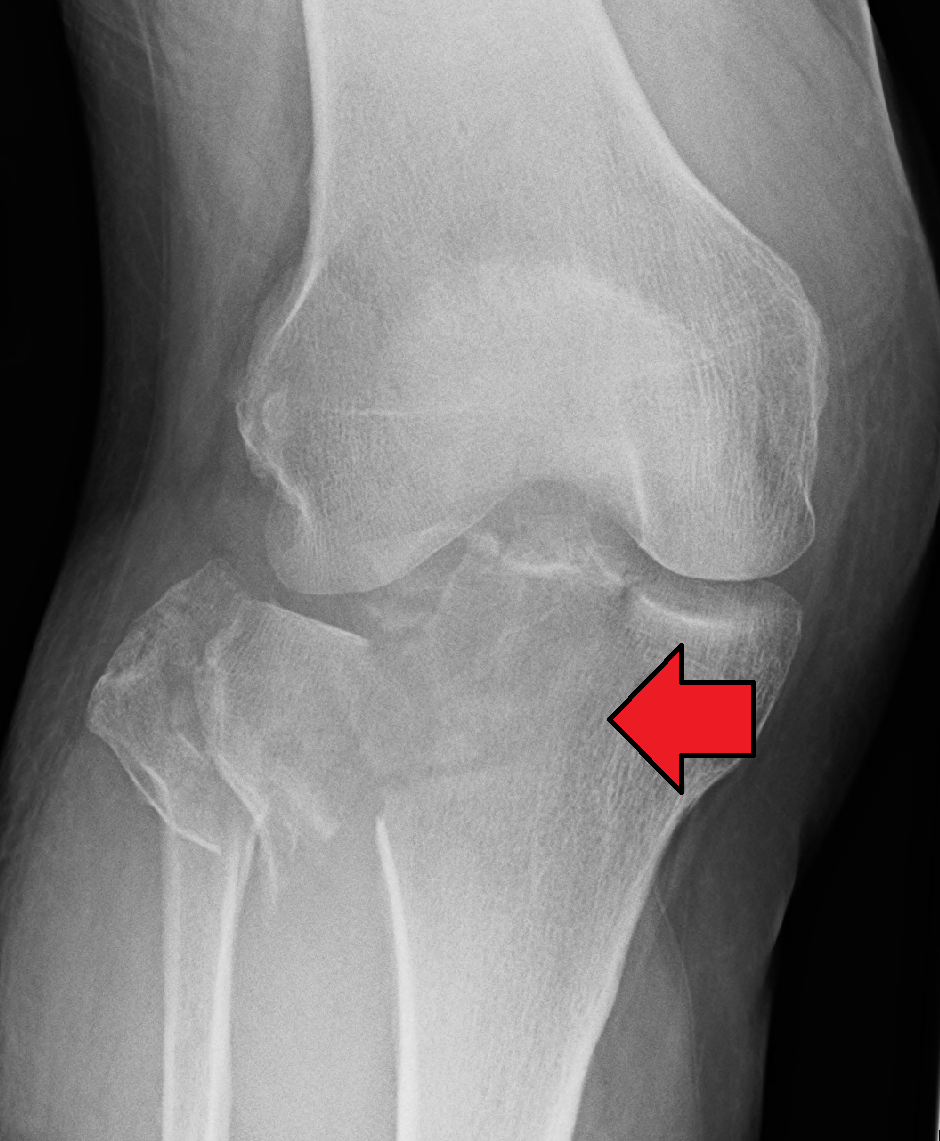

Image: Tibial Plateau Fracture region from Wikipedia

A Tibial Plateau Fracture is typically caused by high-energy forces such as falls, sports injuries, or motor vehicle accidents. The fracture occurs in the bony platform of the tibia that supports the weight-bearing portion of the knee joint. Treatment for Tibial Plateau Fractures often involves surgery, such as open reduction and internal fixation (ORIF), to realign and stabilize the fractured bone fragments.